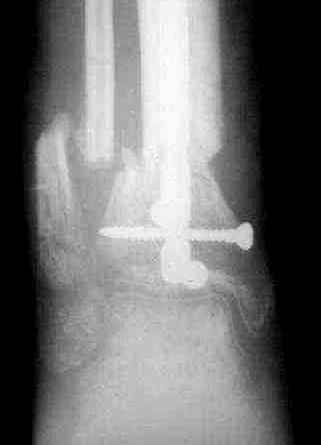

1 - рентгенограмма (прошу прощения за качество) при поступлении;

5, 6 - через 2,5 мес после травмы выполнен закрытый остеосинтез блокируемым штифтом.

7, 8, 9, 10, 11 - через 8 мес после травмы перелом сросся.